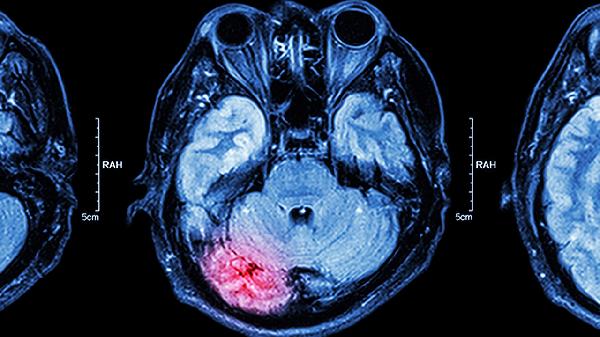

甲状腺癌脑转移的前兆可能包括头痛、恶心呕吐、肢体无力、视力改变、癫痫发作等症状。甲状腺癌脑转移通常由癌细胞通过血液或淋巴系统扩散至脑部引起,可能伴随颅内压增高、神经功能缺损等表现。建议患者及时就医,通过影像学检查明确诊断,并接受针对性治疗。